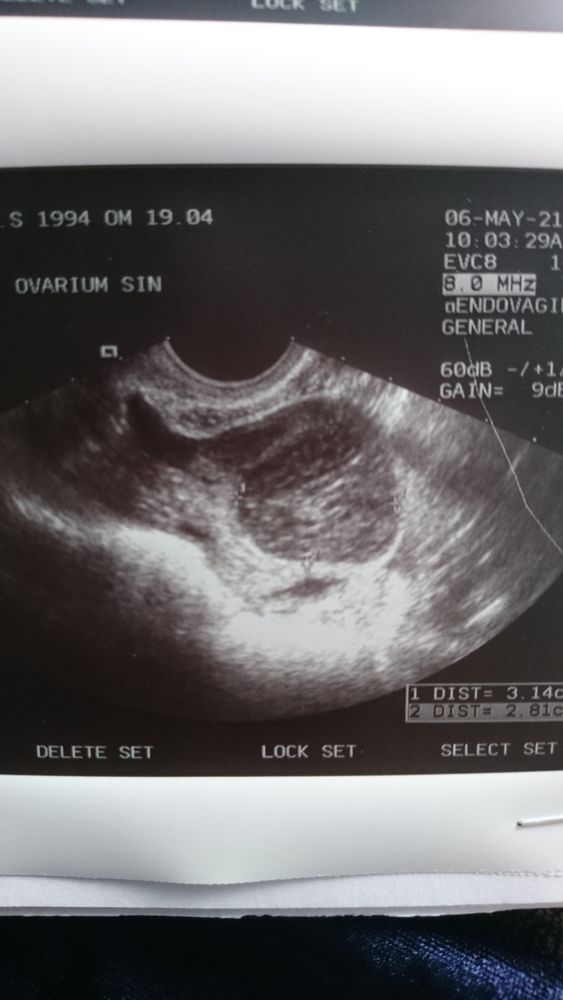

Киста , и не было овуляции .

Ewigkeit, да есть что то ... мне сказали что овуляции не было, и появилась киста . А с прошлых фото по узи, моя киста жт вроде бы так выглядела

Вот так выглядит киста яичника,при чем у меня было сразу в обоих Я в цикле, у Вас скорее всего ЖТ.